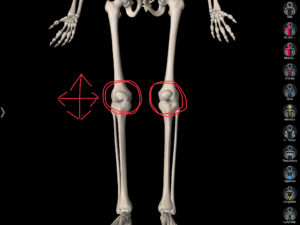

検査をしていると炎症も強く出ていたのですが、膝のお皿の動きが悪く両足の内側の骨が外側に回旋をしていました。

今回の患者さんは膝のお皿の動きが悪くなるにプラスして、膝下の2本あるうちの内側の骨(脛骨/けいこつ)が少し回旋して悪さをしていました。

確認するポイントとしては膝のお皿の横(内側)を少し押してみてください。

↑

(上の赤まるが目印)